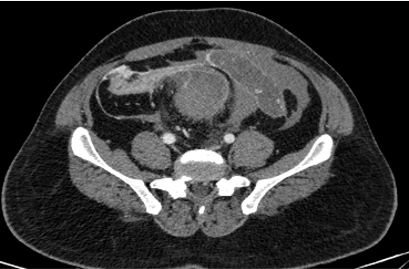

A 54-year-old woman, post-cholecystectomy -10 days back, now came with complaints of abdominal pain and vomiting.

A: Postcholecystectomy status

Post operative Iatrogenic biliary duct injury with bile leak

(Strasberg classification – Type E- E4 )